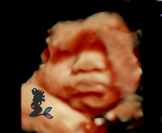

BEFORE

Add to your next 3D4D package

-

Bring life to your images

Professional digital editing

One image for $25 or two for $40

Already have your 3D images, no problem. You can email them to us and we can edit them.

8K image enhancements now available

AFTER